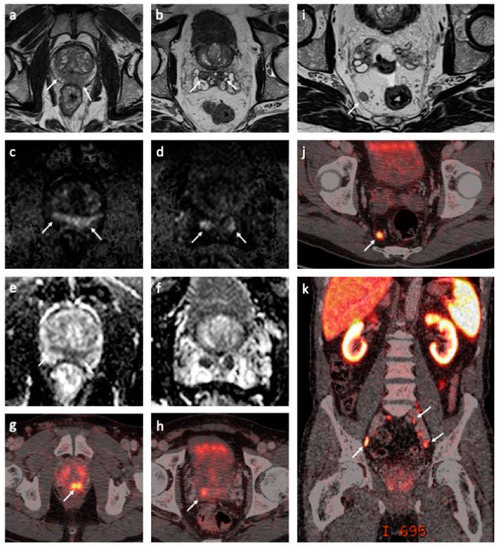

Figure 1. Magnetic resonance imaging (MRI) and prostate-specific membrane antigen (PSMA)-positron emission tomography (PET)/computed tomography (CT) findings at the baseline. Axial T2-weighted MRI sequences demonstrated a large, diffuse infiltrating tumor in the peripheral zone with seminal vesicle invasion ((a,b), white arrows). The tumor was hyperintense on diffusion-weighted MRI (DW-MRI) (b = 1500 s/mm2) ((c,d), white arrows) with a corresponding low apparent diffusion coefficient (ADC) (ADC = 0.6 × 10−3 mm2/s) ((e,f), white arrows). Corresponding tracer uptake on fused PSMA-PET/CT images ((g,h), white arrow). A large lymph node metastasis in the mesorectal fat is shown on the axial T2-weighted MRI ((i), white arrow) and fused PSMA-PET/CT images ((j), white arrow). A coronal-fused PSMA-PET/CT image demonstrates multiple metastases to the pelvic lymph nodes ((k), white arrows).